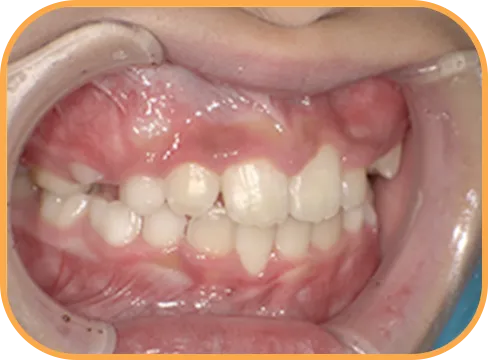

• Before

• 正 面

治療前正面からの歯の様子

• 上 顎

治療前上顎からの歯の様子

• 下 顎

治療前下顎からの歯の様子

• 右 側

治療前右側からの歯の様子

• 左 側

治療前左側からの歯の様子

主 訴

前歯がでている、噛み合わせが深い

治療内容

インビザライン・ファースト

治療期間

10か月

治療費(税別)

450,000円+診断料30,000円

リスク・副作用

• 親知らずの影響や加齢などによって、凸凹が生じる可能性があります。

• 治療の初期段階では痛みや不快感が生じやすくなりますが、1週間前後で慣れます。

• 顎の成長発育によって、噛み合わせや歯並びが変化する可能性があります。

• 状況により当初予定した治療計画を変更する可能性があります。